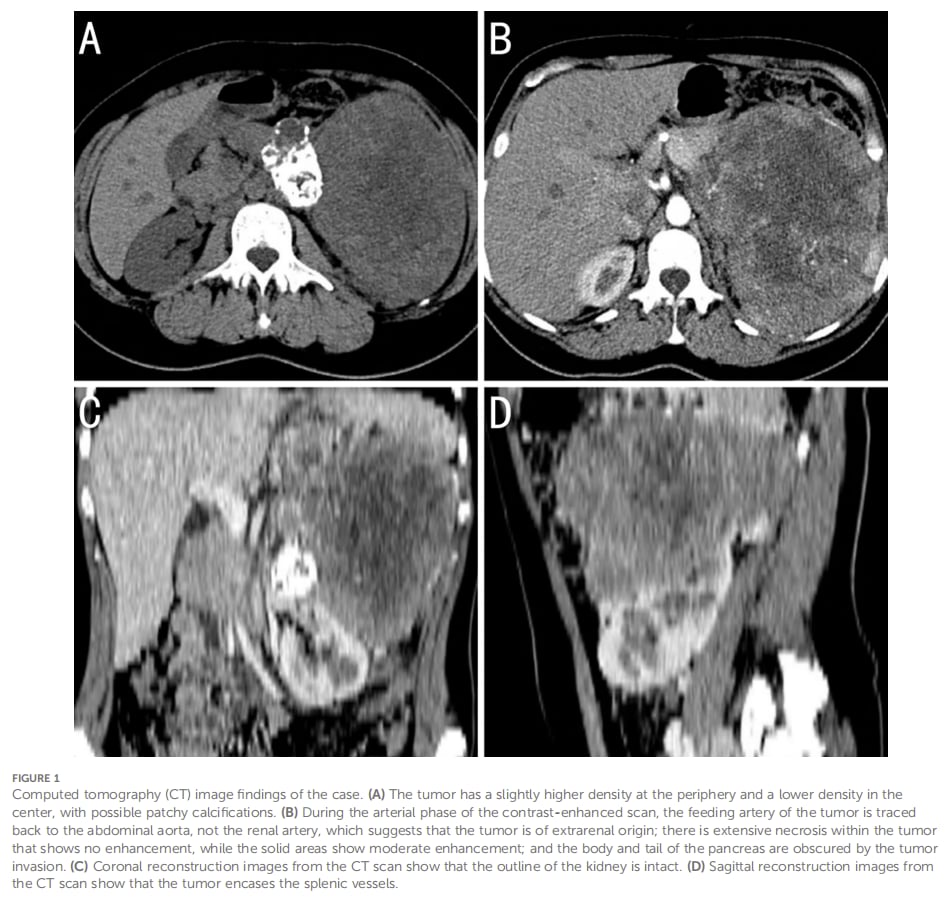

影像显示病灶位于左侧腹膜后,体积很大,呈混合密度,局部钙化,增强后明显不均匀强化,且与胰尾边界不清,左肾受压下移,左侧肾上腺显影不佳。单看这些信息,把它误认为胰尾来源肿瘤并不意外。

腹膜后肿块CT影像显示病灶巨大、强化不均、与邻近器官分界不清,容易造成原发部位判断偏差。